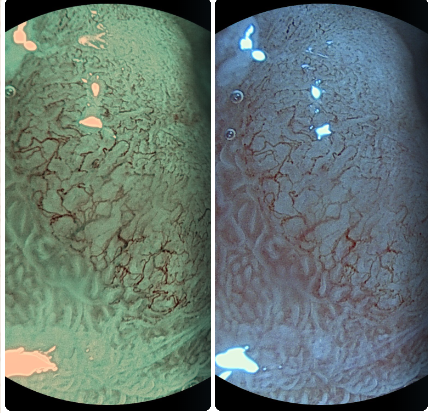

CROMOENDOSCOPIA GÁSTRICA Y MAGNIFICACIÓN

Es una técnica avanzada que utiliza colorantes y aumento óptico para observar con gran detalle la musoca del estómago.

Permite identificar lesiones muy pequeñas y detectar de forma precoz cambio precancerosos o cáncer gástrico en fases iniciales.